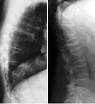

000000000233.jpg Fracture vertébrale de grade 3 du rachis lombaireMiniaturesFractures vertébralesFracture vertébrale de grade 3 du rachis lombaireMiniaturesFractures vertébralesFracture vertébrale de grade 3 du rachis lombaireMiniaturesFractures vertébralesFracture vertébrale de grade 3 du rachis lombaireMiniaturesFractures vertébralesFracture vertébrale de grade 3 du rachis lombaireMiniaturesFractures vertébrales

Aspects IRM des fractures ostéoporotiques vertébrales.